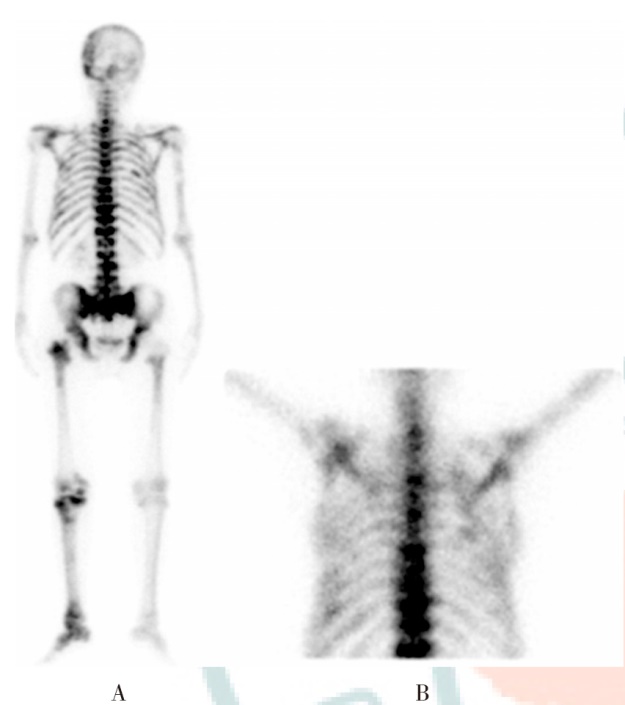

目的 探究发射计算机断层显像(ECT)联合血清成纤维细胞生长因子23(FGF23)、血管生成素样蛋白2(Angptl-2)对肺癌患者骨转移的诊断价值。方法 选取2023年6月至2025年6月西安交通大学第一附属医院收治的127例肺癌疑似骨转移患者为研究对象。ELISA法检测血清FGF23、Angptl-2水平;采用Bayesian log-binomial回归模型分析评估FGF23、Angptl-2水平对肺癌患者发生骨转移的影响;受试者操作特征(ROC)曲线评估血清FGF23、Angptl-2水平对肺癌患者骨转移的诊断效能;四格表法分析ECT联合血清FGF23、Angptl-2水平对肺癌患者骨转移的诊断价值。结果 以骨活检病理结果为金标准,127例肺癌疑似骨转移患者中发生骨转移53例,无骨转移74例。骨转移患者血清FGF23、Angptl-2水平分别为(123.46±22.18)pg/ml、(32.46±5.13)ng/ml,无骨转移患者分别为(98.37±16.21)pg/ml、(26.52±4.15)ng/ml,与无骨转移患者相比,骨转移患者血清FGF23、Angptl-2水平均较高,差异均有统计学意义(t=7.37,P<0.001;t=7.20,P<0.001)。血清FGF23、Angptl-2高水平患者发生骨转移的风险分别是低水平患者的2.96倍、2.66倍。ROC曲线分析显示,血清FGF23、Angptl-2水平诊断肺癌患者骨转移的曲线下面积(AUC)分别为0.77、0.81,敏感性分别为69.81%、66.04%,特异性分别为82.43%、87.84%,准确性分别为77.17%、78.74%。ECT诊断肺癌患者骨转移的敏感性为79.25%,特异性为83.78%,准确性为81.89%。ECT联合血清FGF23、Angptl-2诊断肺癌患者骨转移的敏感性为98.11%,特异性为81.08%,准确性为88.19%,联合诊断的敏感性均高于血清FGF23、Angptl-2、ECT各自诊断(χ2=15.76,P<0.001;χ2=18.53,P<0.001;χ2=9.40,P=0.002),联合诊断的准确性均高于血清FGF23、Angptl-2各自诊断(χ2=5.39,P=0.020;χ2=4.11,P=0.043)。结论 肺癌骨转移患者血清FGF23、Angptl-2水平均较高,ECT联合血清FGF23、Angptl-2水平较各指标单独检测对肺癌患者骨转移的诊断价值更高。

Objective To explore the diagnostic value of emission computed tomography (ECT) combined with serum fibroblast growth factor 23 (FGF23) and angiopoietin-like protein 2 (Angptl-2) for bone metastasis in lung cancer patients. Methods A total of 127 patients suspected of having bone metastasis from lung cancer at First Affiliated Hospital of Xi'an Jiaotong University from June 2023 to June 2025 were included as the study subjects. ELISA method was used to measure the levels of serum FGF23 and Angptl-2. The Bayesian log-binomial regression model was used to evaluate the effects of the levels of FGF23 and Angptl-2 on bone metastasis in lung cancer patients. Receiver operator characteristic (ROC) curve was used to analyze the diagnostic efficacy of serum FGF23 and Angptl-2 levels for bone metastasis in lung cancer patients; Four grid table method was used to analyze the diagnostic value of ECT combined with serum FGF23 and Angptl-2 levels for bone metastasis in lung cancer patients. Results Taking the pathological results of bone biopsy as the gold standard, among 127 patients with suspected bone metastasis of lung cancer, 53 cases had bone metastasis and 74 cases didn't have bone metastasis. The levels of serum FGF23 and Angptl-2 in patients with bone metastasis were (123.46±22.18) pg/ml and (32.46±5.13) ng/ml, respectively, while those in patients without bone metastasis were (98.37±16.21) pg/ml and (26.52±4.15) ng/ml, respectively. Compared with patients without bone metastasis, the levels of serum FGF23 and Angptl-2 in patients with bone metastasis were both relatively higher, with statistically significant differences (t=7.37, P<0.001; t=7.20, P<0.001). The risk of bone metastasis in patients with high levels of serum FGF23 and Angptl-2 was 2.96 times and 2.66 times that of patients with low levels, respectively. The ROC curve analysis showed that, the area under the curve (AUC) of serum FGF23 and Angptl-2 levels in diagnosing bone metastasis in lung cancer patients was 0.77 and 0.81, respectively, the sensitivities were 69.81% and 66.04%, respectively, the specificities were 82.43% and 87.84%, respectively, and the accuracies were 77.17% and 78.74%, respectively. The sensitivity of ECT in diagnosing bone metastasis in lung cancer patients was 79.25%, the specificity was 83.78%, and the accuracy was 81.89%. The sensitivity of ECT combined with serum FGF23 and Angptl-2 in diagnosing bone metastasis in lung cancer patients was 98.11%, the specificity was 81.08%, and the accuracy was 88.19%. The sensitivity of combined diagnosis was higher than that of serum FGF23, Angptl-2 and ECT alone (χ2=15.76, P<0.001; χ2=18.53, P<0.001; χ2=9.40, P=0.002), and the accuracy of combined diagnosis was higher than that of serum FGF23 and Angptl-2 alone (χ2=5.39, P=0.020; χ2=4.11, P=0.043). Conclusions Patients with lung cancer bone metastasis have higher levels of serum FGF23 and Angptl-2. ECT combined with serum FGF23 and Angptl-2 levels has a higher diagnostic value for bone metastasis in lung cancer patients compared to the individual detection of each indicator.